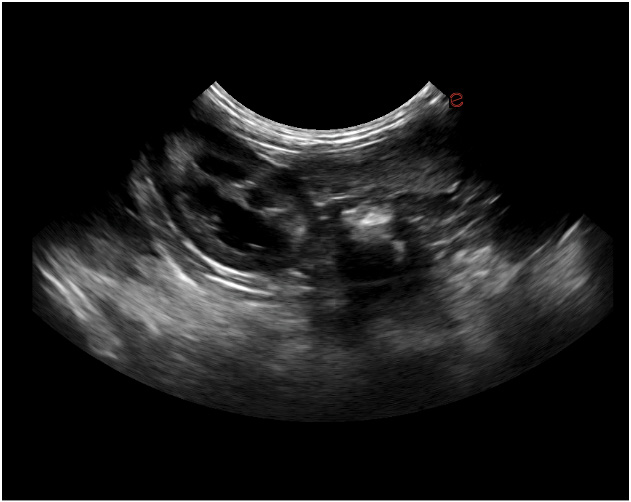

Esaote Q7 Vet er et trådløst, håndholdt ultralydapparat dedikert for veterinærer. Spesialtilpassete forhåndsinnstillinger og software og database designet for dyr. Esaote Q7 kombinerer kraften til moderne ultralydteknologi med brukervennlighet og mobilitet.

Med håndholdt ultralyd og en smartmobil/nettbrett, kan du gjøre raske og gode undersøkelser med Esaote Q7. Dets trådløse design gjør det mulig å utføre ultralydundersøkelser av høy kvalitet når som helst og hvor som helst. Alt er tilrettelagt for en vellykket undersøkelse.